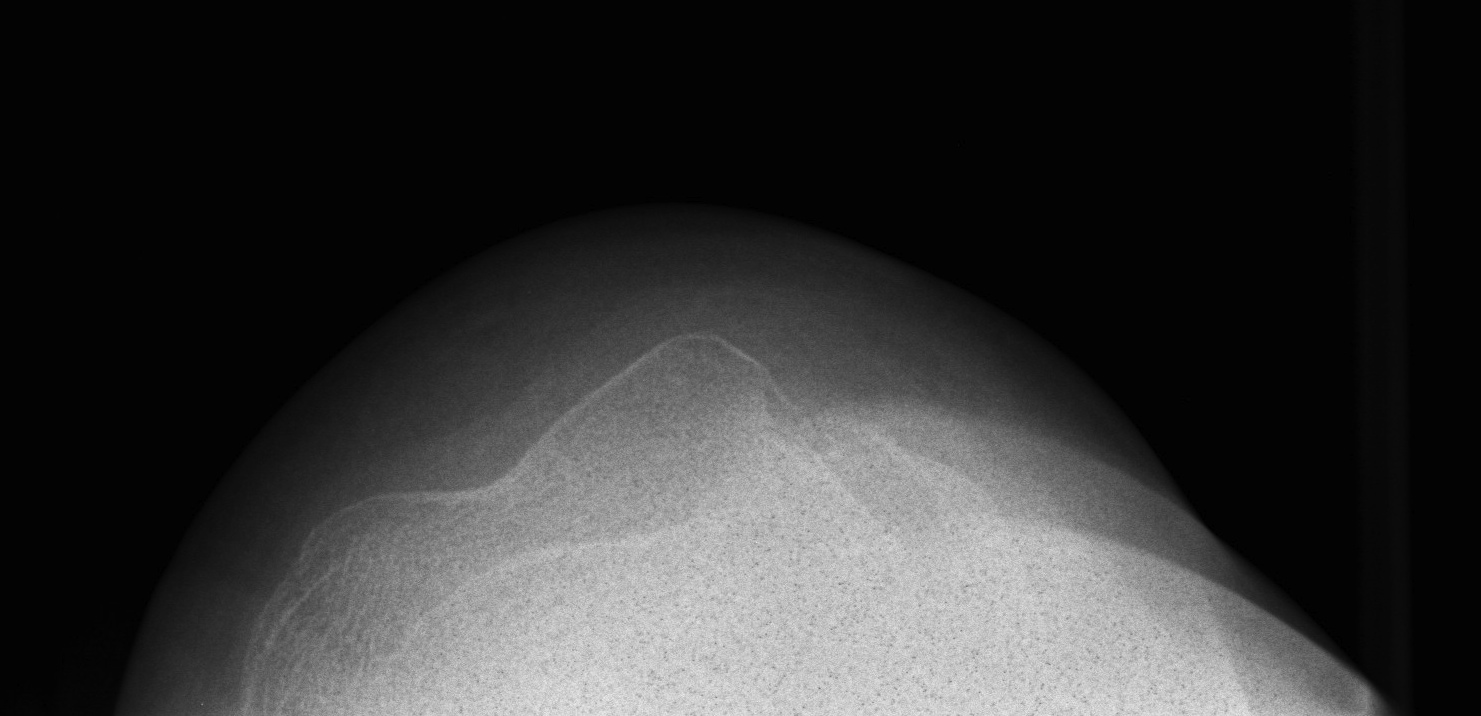

1. Direct lateral blow to patella

- usually with knee partly flexed and quadriceps relaxed

2. Indirect low energy injury

Repeated dislocation of patella with minimal trauma

- 15-20% of paediatric acute patella dislocations

- more common girls

- often bilateral

Dislocation occurs unexpectedly when quadriceps contracted with knee in flexion